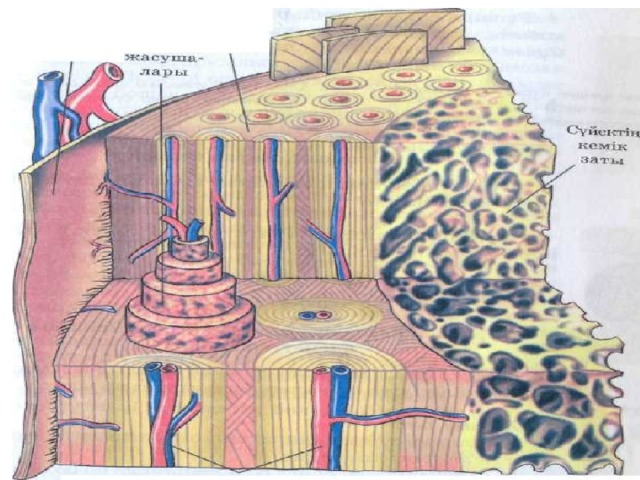

Структура грубоволокнистой костной ткани: наглядные примеры